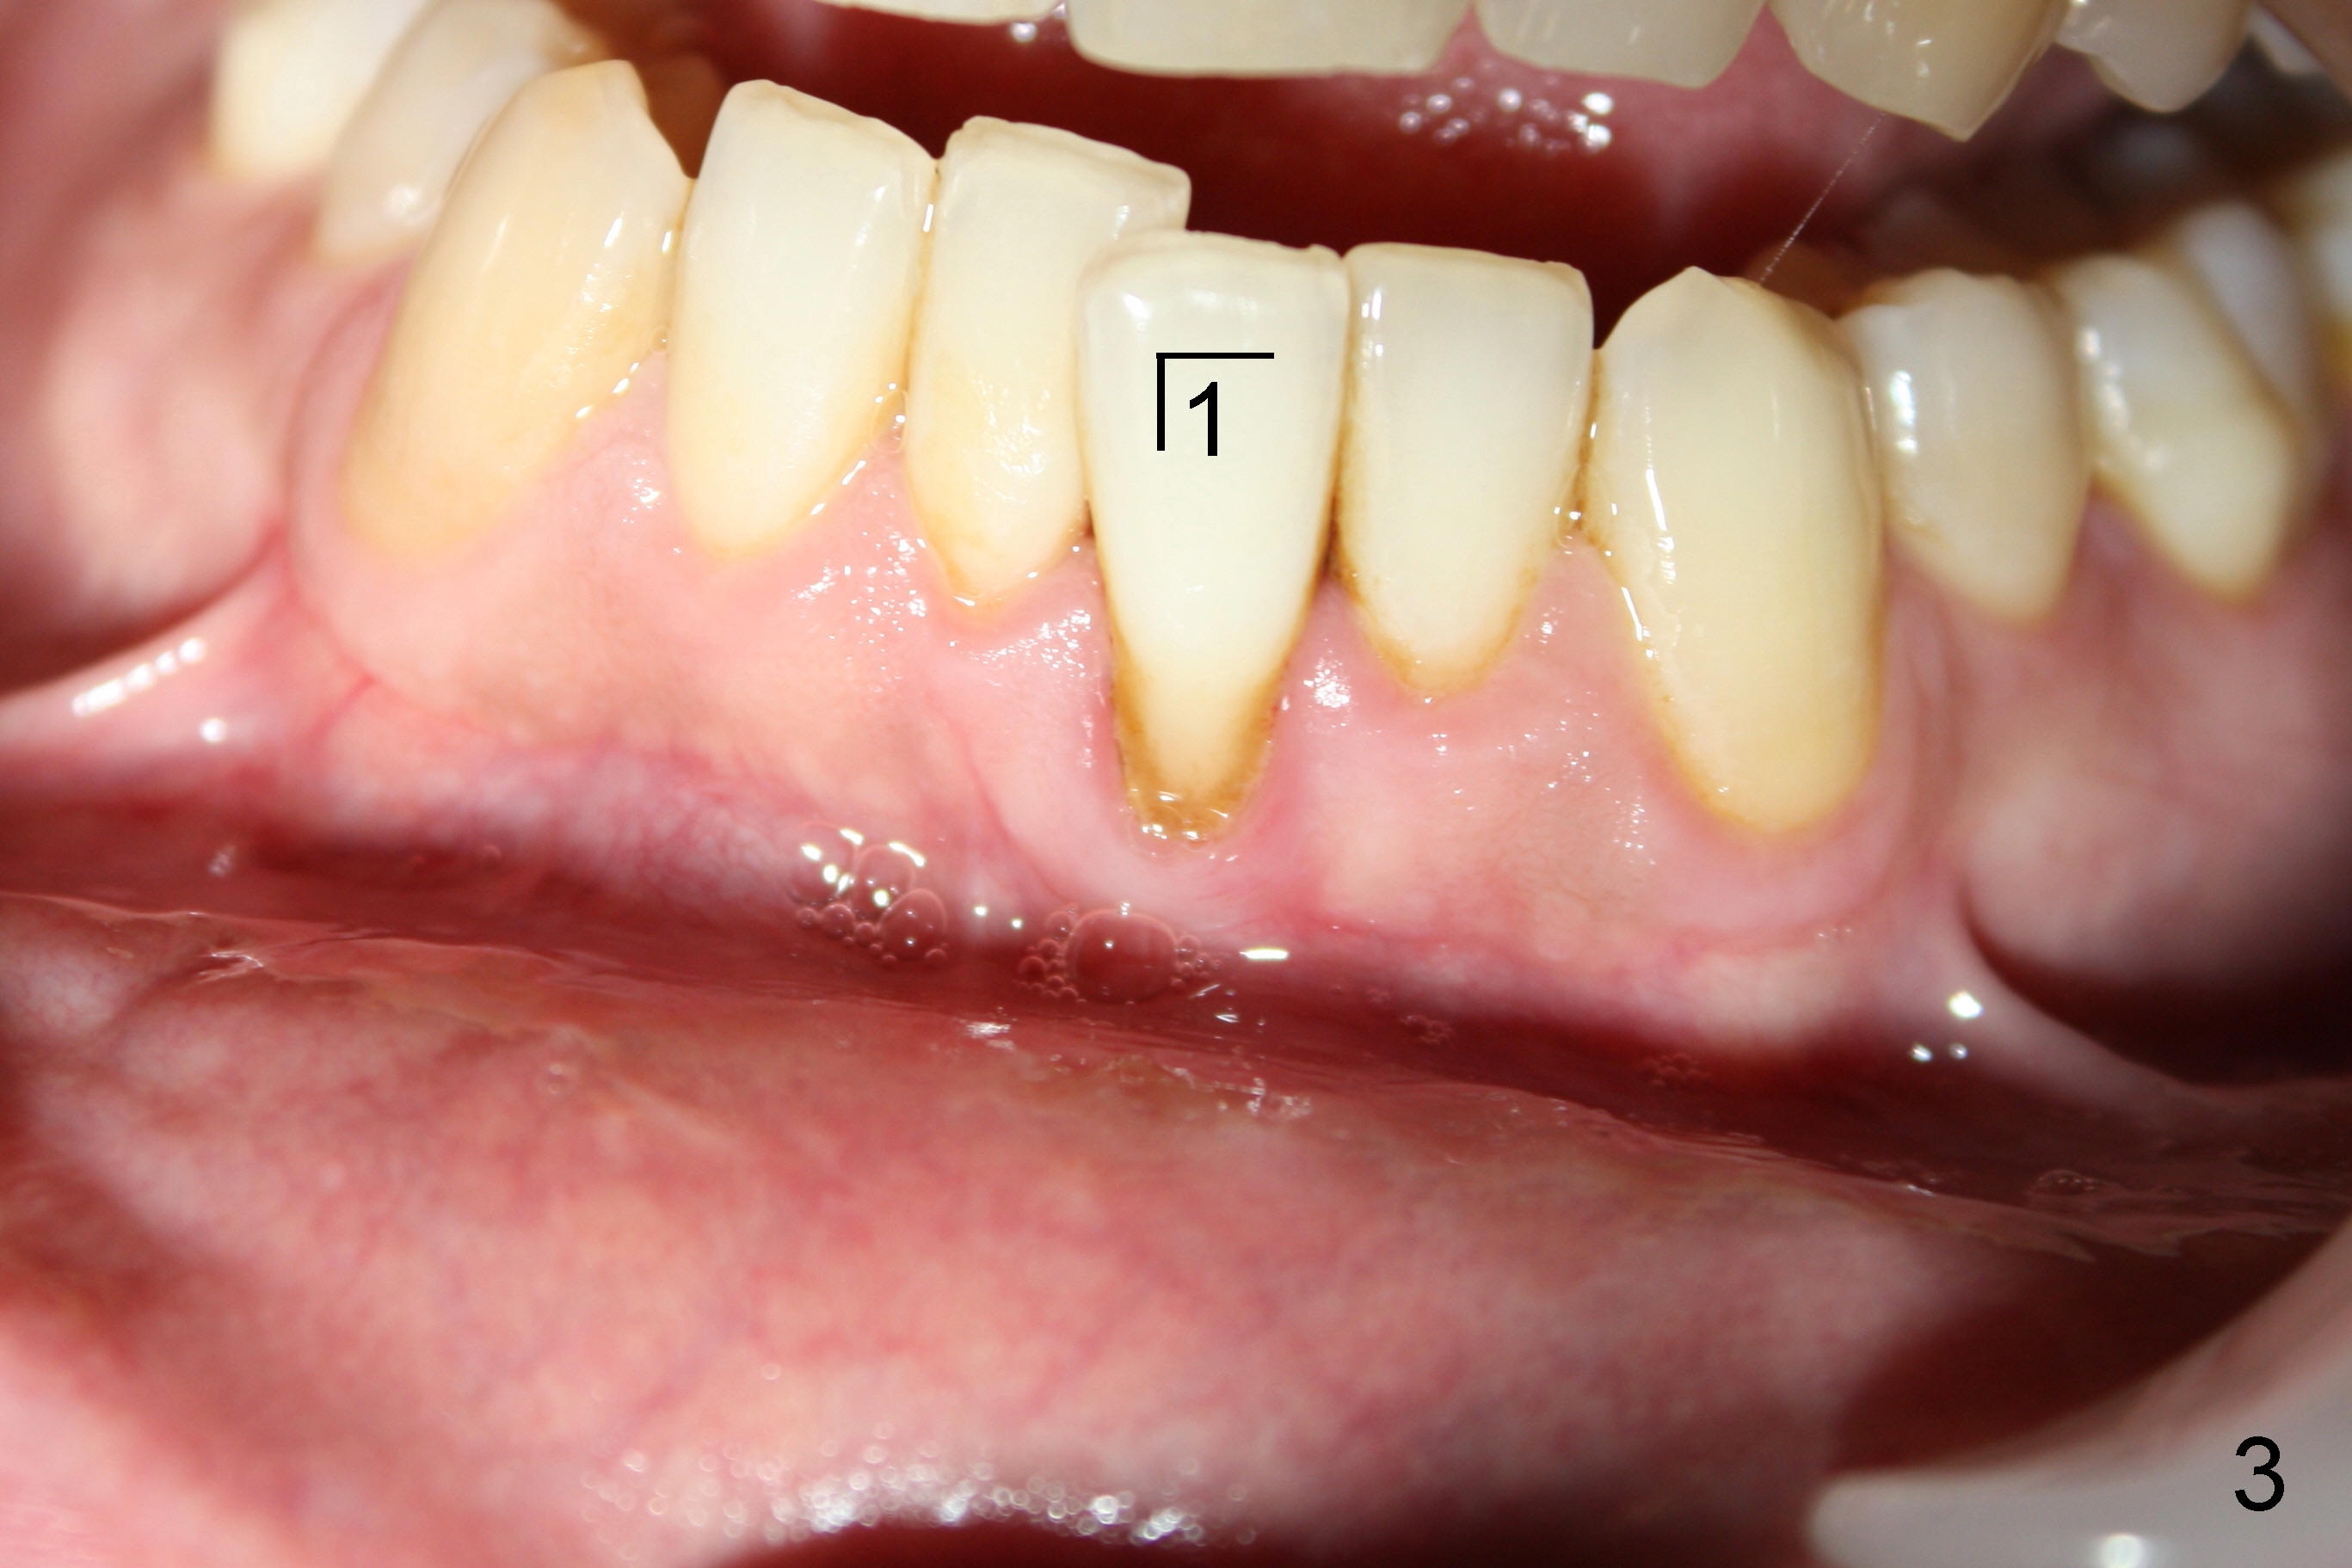

Forty-year-old man had ortho with extraction in his teens (Fig.1,2: B: bicuspid). Without wearing retainers, relapse occurs, particularly in the lower anterior. The lower left central incisor shifts labially with gingival recession (Fig.2,3). The attached gingiva is narrow for this incisor as compared to that of the neighboring tooth (Fig.4 between arrowheads). Although there is abundance of calculus, bone loss is mild to moderate (Fig.5-7). Scaling and root planing was finished today with schedule of perio maintenance every 3 months.

Both arches are narrow (Fig.1,2). Will be there space to move the lower left central lingually? Once the tooth is in normal position, gingival graft is performed to correct recession.